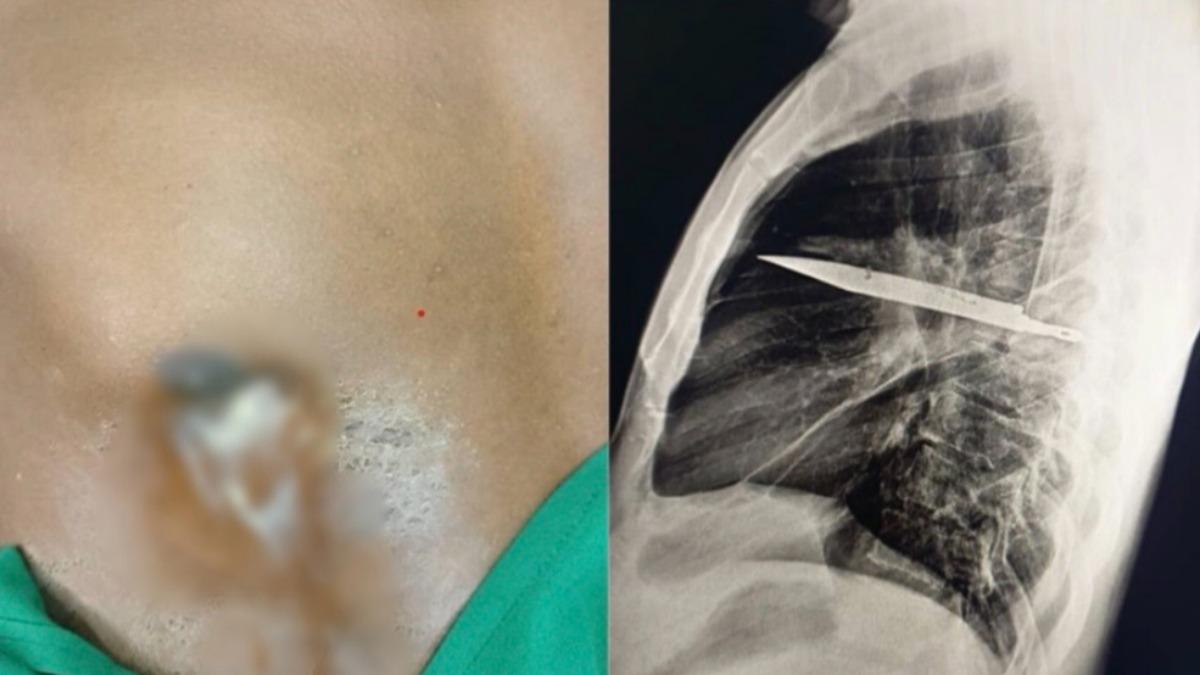

TVBS

苗栗縣2025年10月中破獲一起柬埔寨跨境運輸海洛因毒品案,檢警查出49歲蘇姓女子、46歲羅姓女子和38歲葉姓男子等3人,涉嫌接受販毒集團招待,以10到15萬元的代價,前往柬埔寨旅遊一個星期,條件是要吞下層層包裹保護的海洛因毒球,返台後再排出交貨,後續警方逮捕3人,並在體內找到26顆毒球,今(12)日檢方依《毒品危害防制條例》將3人起訴,持續擴大追查中。